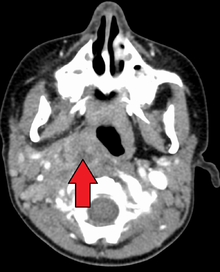

A computed tomography (CT) scan is the definitive diagnostic imaging test.[4]

X-ray of the neck often (80% of the time) shows swelling of the retropharyngeal space in affected individuals. If the retropharyngeal space is more than half of the size of the C2 vertebra, it may indicate retropharyngeal abscess.[5]